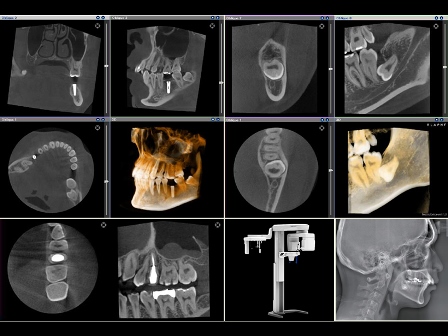

CT

3次元的に画像を診断する事ができるので、インプラント治療・歯周治療・顎関節症治療・歯内療法治療・外科治療等でより正確な診断が出来ます。